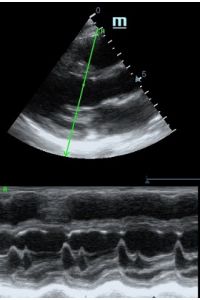

Но как же провести стандартные измерения в М-режиме, если мы его не использовали? На помощь приходит функция Free Xros M – анатомический М-режим. Имея записанную в память прибора видео петлю, мы можем провести линию М-режима в любом месте, при этом корректируя изначально не оптимальный угол.

Возможности применения функции многогранны: от измерения толщины стенок левого желудочка, движения створок митрального клапана и кооптации нижней полой вены до оценки сократимости миокарда как глобально, так и по сегментам.